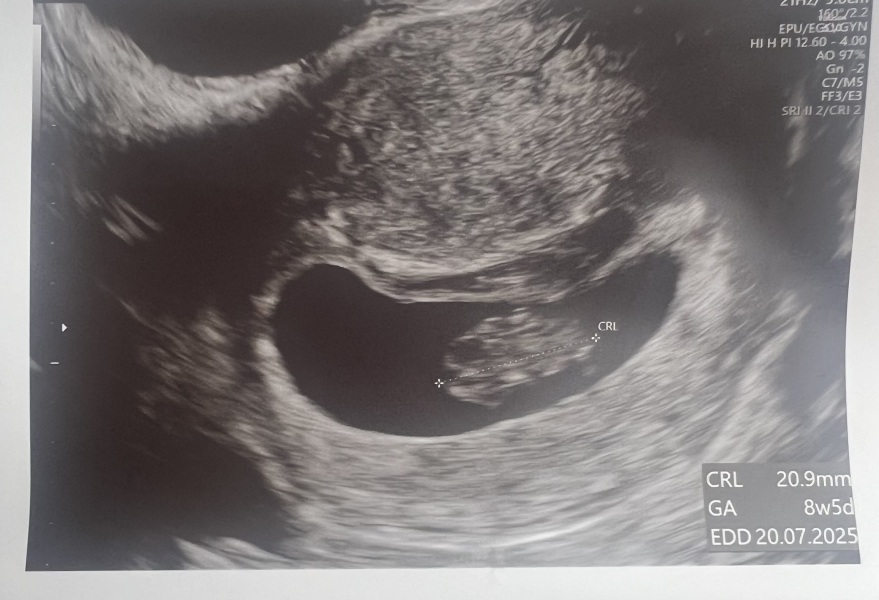

Scan went well! Measuring right on dates at 8 weeks 4 days ish, heartbeat strong at 176 which I thought is at upper end though? Saw little stubs of arm and leg wriggling around…all very surreal. Know it’s just a snapshot and still really early but relieved that as far as you can see everything is as good as it can be! Thanks for support ladies Flowers

Hope everyone else who was having scans went ok x